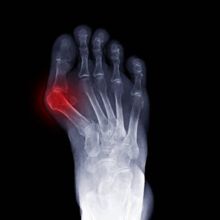

Hallux valgus - vbočený palec